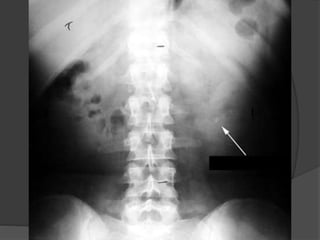

Imaging

 Plain abdominal radiography

 KUB radiography

 size, shape, and location of urinary calculi

 Radiopaque

○ Calcium-containing stones,

○ Cystine

○ struvite stones are

 Radiolucent

○ pure uric acid